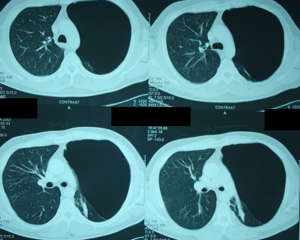

Εικόνα 2γ

Αξονική τομογραφία του θώρακος. Τομή στο ύψος της αριστερής κάτω

Πνευμονικής φλέβας. Το αριστερό ημιθωράκιο συνεχίζει να

καταλαμβάνεται από αερώδεις κύστες, ενώ αρχίζει να διακρίνεται πνευμονικό παρέγχυμα.

Εικόνα 2δ

Αξονική τομογραφία του θώρακος. Τομή πάνω από το επίπεδο του

διαφράγματος. Διακρίνεται περισσότερο πνευμονικό παρέγχυμα, ενώ

συνεχίζουν να διακρίνονται αερώδεις κύστες.

Εικόνα 2ε

Αξονική τομογραφία του θώρακος. Τομή στο επίπεδο του διαφράγματος.

Μεικτή εικόνα, αερωδών κύστεων και πνευμονικού παρεγχύματος.